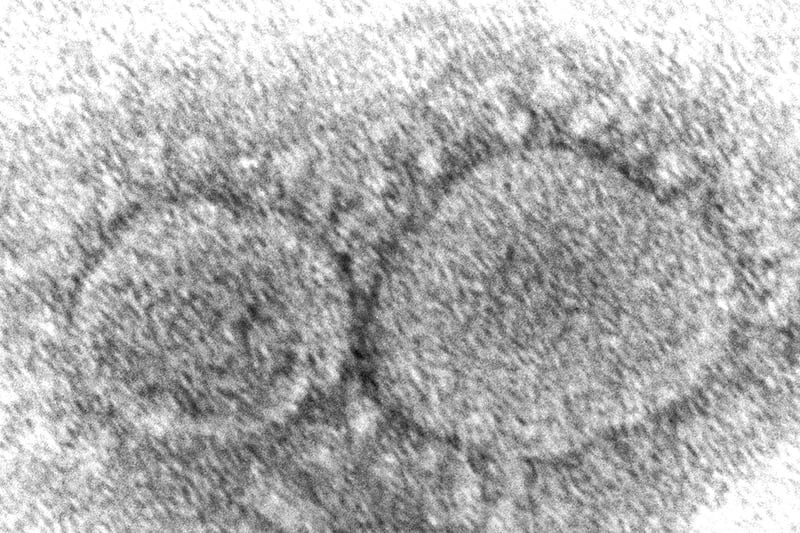

The latest omicron variant BA.4.6 is gaining ground and already accounts for 9.2% of new cases. An Associated Press report suggests that this new omicron subvariant is “even better at evading the immune system” than the fast-spreading BA.5.

Emerging research also points out that the virus is mutating to become more immunity evasive.